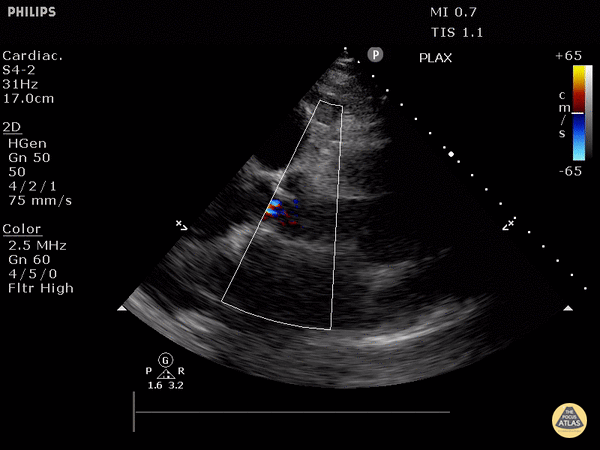

https://www.thepocusatlas.com/valvulopathy

View: Unspecified Parasternal Long Axis Parasternal Short Axis Apical Four-Chamber Subcostal Four-Chamber Subcostal Inferior Vena Cava Right Upper Quadrant Left Upper Quadrant Suprapubic Longitudinal Suprapubic Transverse Subxiphoid Anterior Thoracic Phrenic